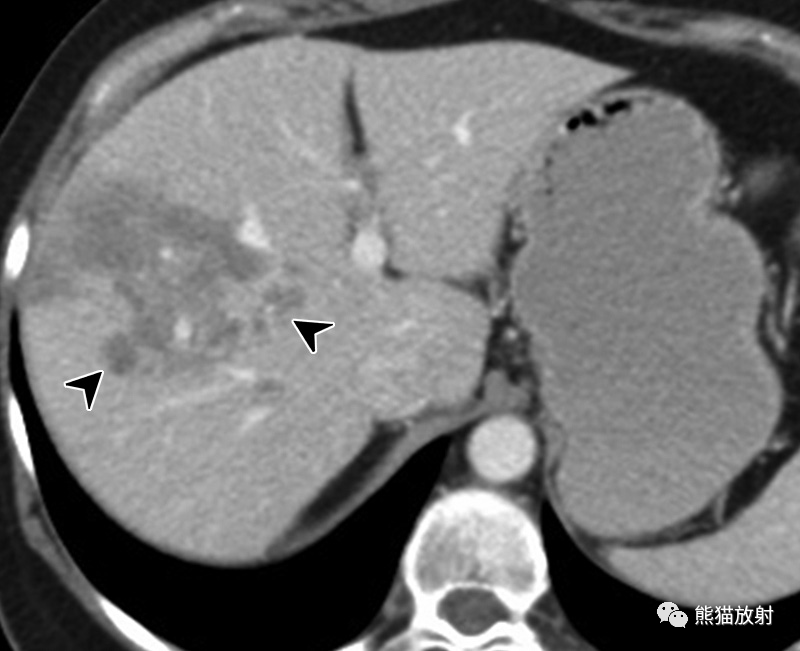

45岁女性,化脓性肝脓肿,表现为发热和胸膜炎性胸痛。(a) 轴位对比增强门脉期CT图像显示肝右叶后段紧贴右侧横膈的多房性囊性肿块。注意壁分层(“双靶征”),内部强化的脓肿膜(箭)被低密度的肝实质水肿(箭头)包围。(b) 轴位增强延迟期CT图像显示内层持续强化,外层延迟强化(箭),多个小房聚集呈“簇征”。